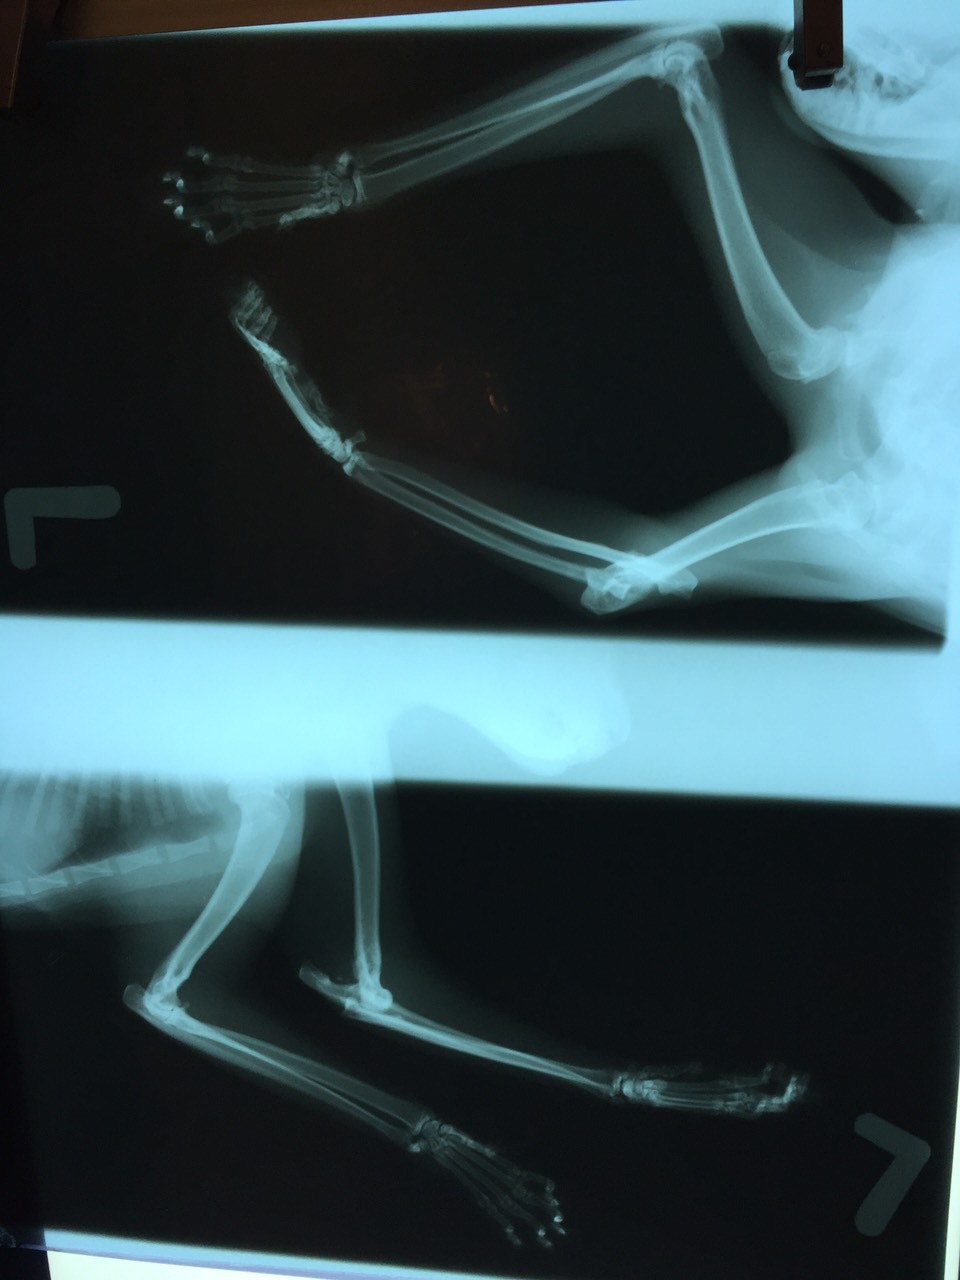

主題: 左前腳嚴重脫臼導致腳掌萎縮變形 申請者姓名: 蔡秀如 花色: 申請日期: 2016-04-07 14:57:27 申請者部落格: 申請者臉書網址: 所在縣市/合作醫院: 台北市/長沁動物醫院 治療費用: 24240元 需求人數: 27人 已結案 (2024-06-01 13:39:19) 報名人員: Jack Wei x3(已付款)、Eric Chien(已付款)、王琇盈(已付款)、Ikkuka(已付款)、薔薔(已付款)、karenla(已付款)、Joe liu x2(已付款)、Nix Lin(已付款)、Maggie Chen(已付款)、poppy(已付款)、KARMA COFFEE(已付款)、圓滾滾的魚尾(已付款)、Anita Lu(已付款)、Mibo Wang、shirley yang(已付款)、薇薇安(已付款)、薇薇安、SihKi Lin(已付款)、陳吉寶(已付款)、柯凱茹(已付款)、Man Tou Park(已付款)、Sky Lin(已付款)、Emily Yen(已付款)、Irene Hu(已付款)、張禾空間設計工作室(已付款)、Sarah(已付款)、 候補人員: 動物病情說明: 二週多前 (2/18) 下班回家經過巷口看到原本常在我家對面二樓屋簷散步的喵咪左前腳受傷了, 由於喵咪腳都是縮著, 連餵食的時候也是, 當時不知道到底有多嚴重,很擔心會感染, 2/23寫 EMAIL 向 TNR 協會尋求協助, 協會立刻請了我家附近的志工蔡小姐跟我聯繫,也於 2/25 晚上順利誘捕後於 2/26晚上在蔡小姐幫忙下將喵咪送到長沁動物醫院救治,醫生照了 X 光說情況很嚴重, 腳傷應該有一段時間了, 已經有長了一些結蒂組織, 我不希望喵咪截肢,請張醫生儘量幫忙將喵咪的腳接回去, 張醫師花了近 4 小時幫海鮮動手術, 很感謝張醫師跟志工蔡小姐 動物近況說明: 海鮮已於 4/2 下午出院了, 目前先帶到我媽家觀察左前腳開刀復原情況